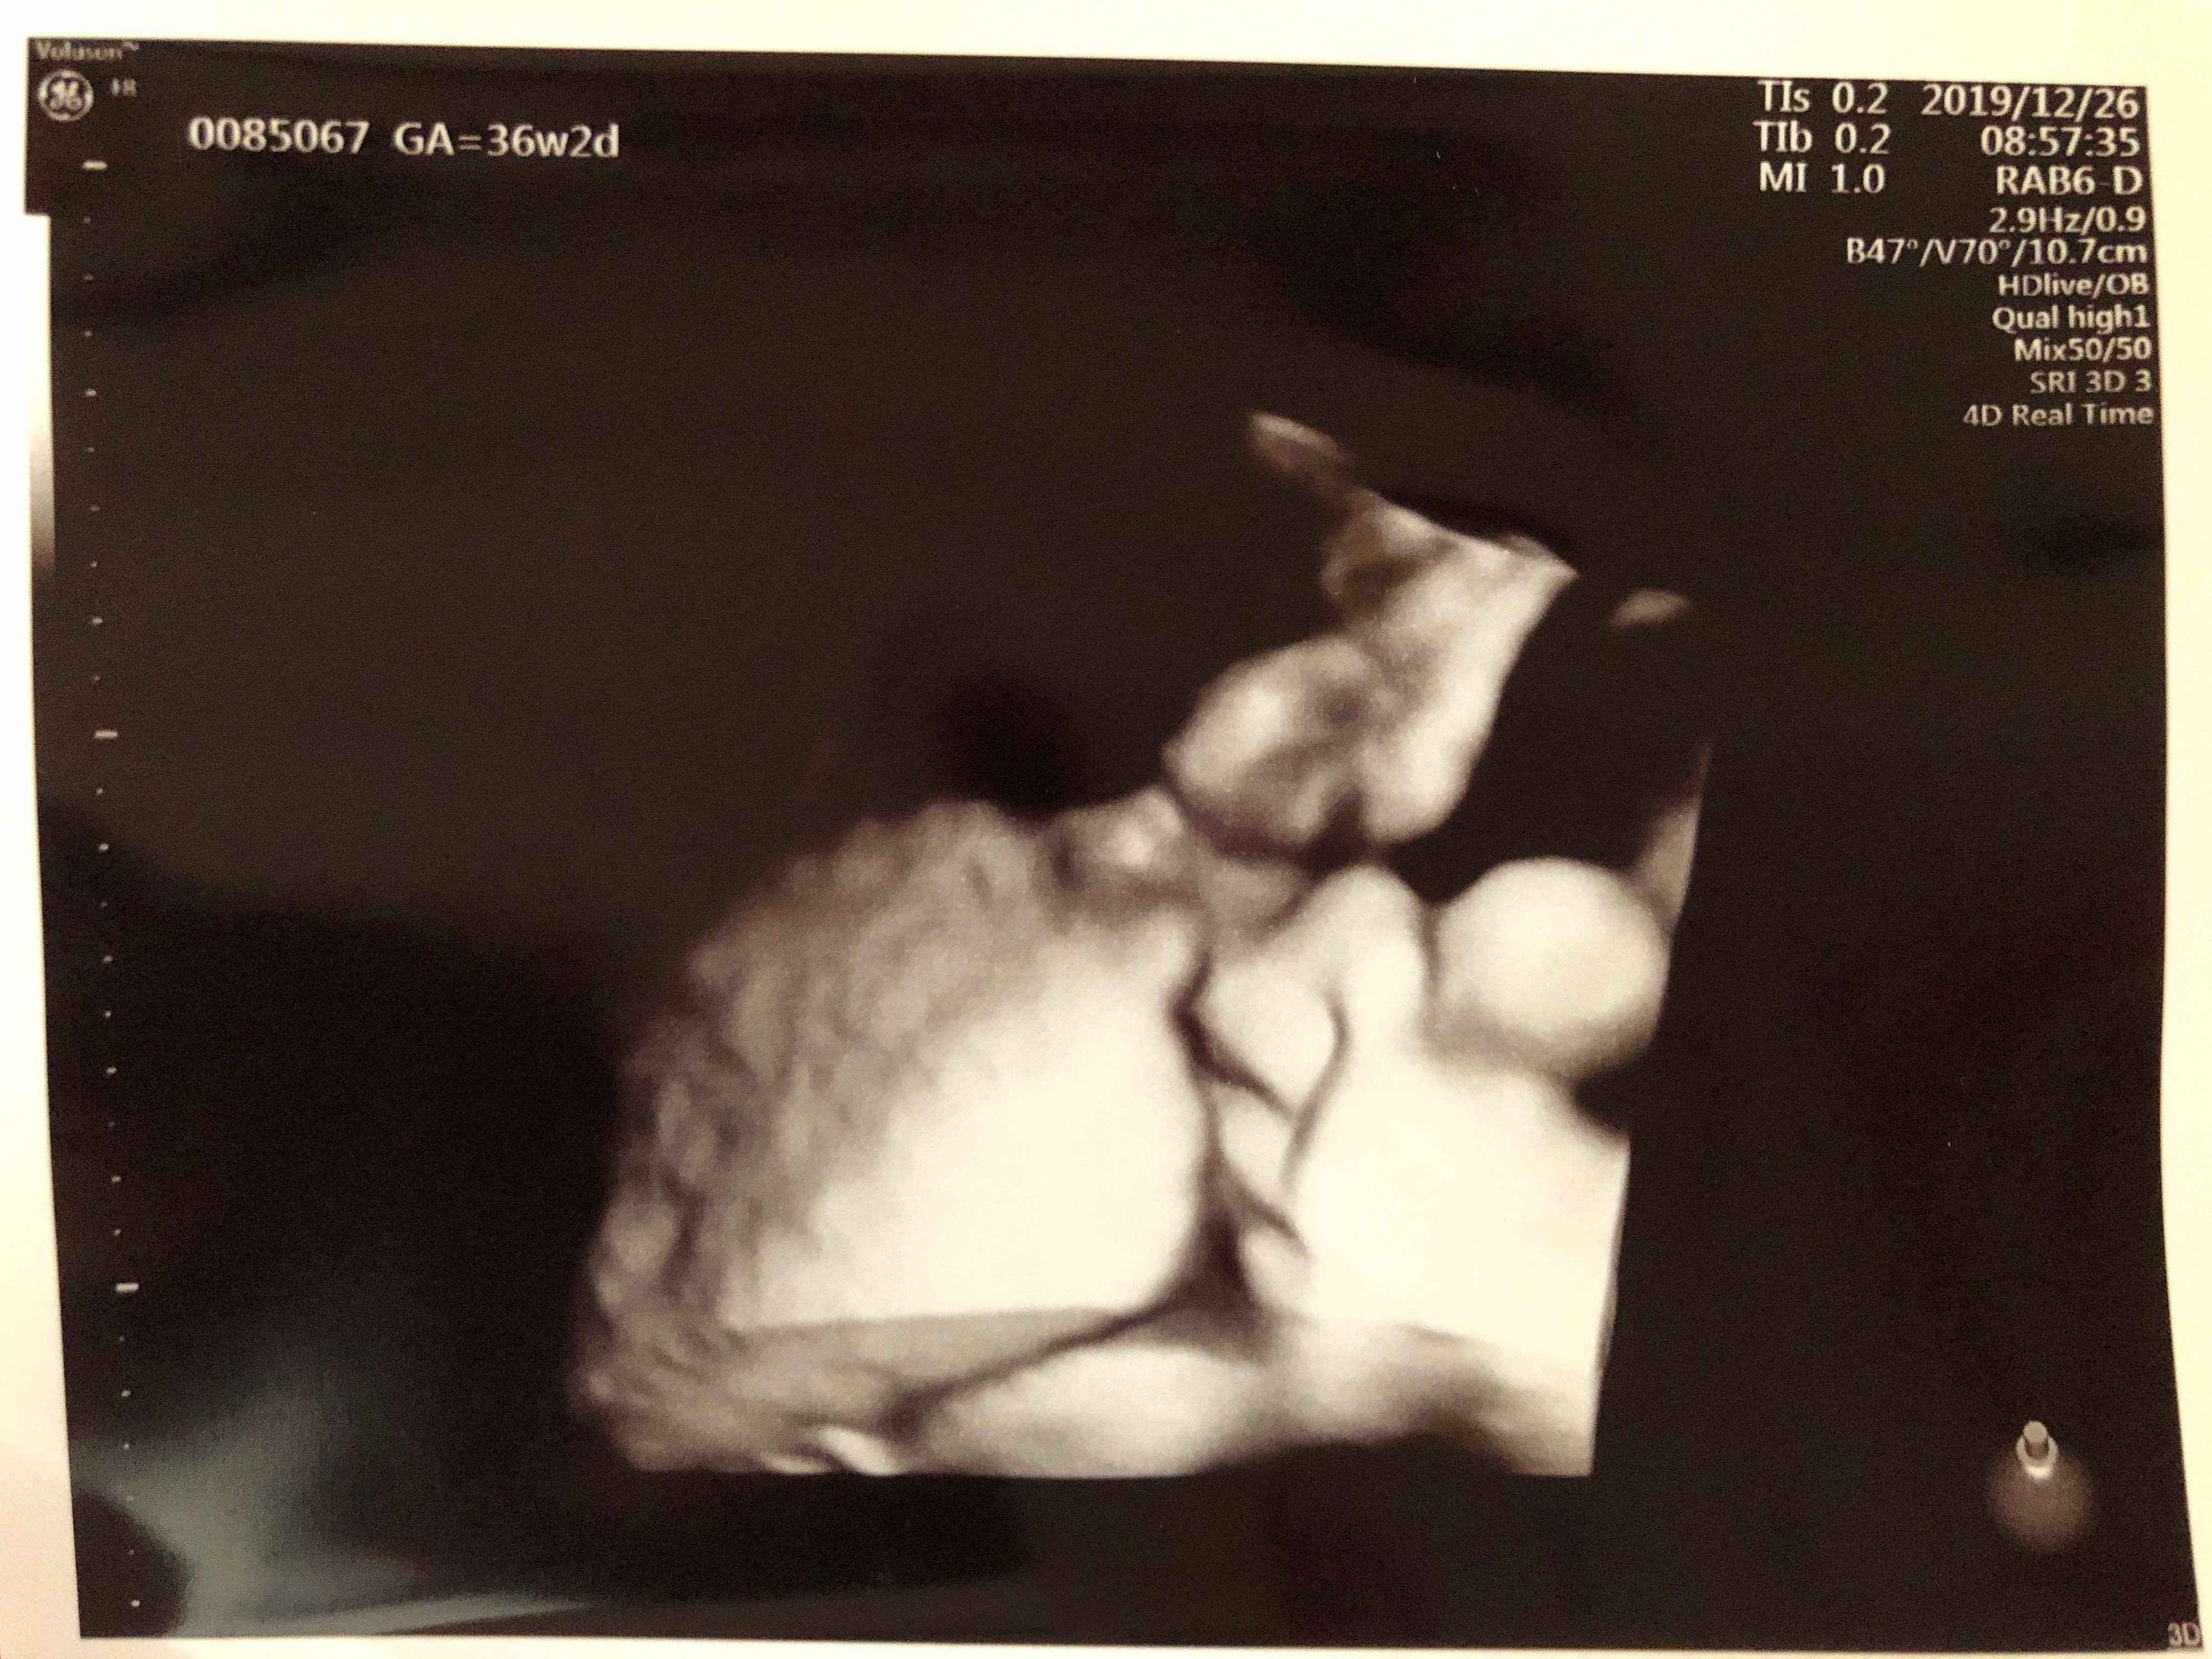

妊娠36週目 大きいおなかにびっくり

妊娠36週、年末年始のお休み前に健診へ。指しゃぶりしている姿を見せてくれました。

「すでに子宮口が2cmほど開いている」と先生に言われ、出産が近づいてきたことを実感しました。推定体重は長男の同じ頃とあまり変わりませんでしたが、おなかがとても大きく、当時1歳になったばかりの長男の抱っこやお風呂に苦労しました。

長男とのスキンシップは、ハグや添い寝で補うようにしていました。